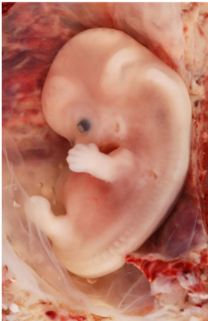

• Embrión

Durante la 12va semana se desarrolla en sistema nervioso, los esbozos de la columna vertebral y del cerebro.

Embrión

Comienza el desarrollo de las extremidades superiores e inferiores.

• Apreciación del feto

Apreciación del feto

Las extremidades y forma del feto se pueden apreciar de forma clara.